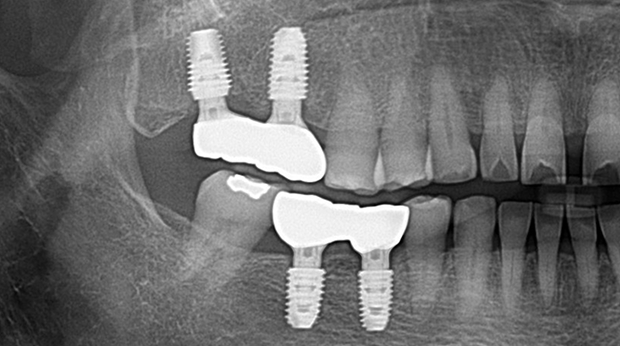

고난도 수술 진료

임플란트와 사랑니 발치는 외과적 시술로 잇몸을 절개하는 외과적 시술은

짧으면 짧을 수록 시술 후 붓기와 통증이 최소화됩니다.

치과의사 경력 14년차 구강외과 전문의가 빠르고 안전하게, 아프지 않게 수술해 드립니다.

치과경력 14년차 구강외과 전문의

연세대학교 치과대학 구강외과 임상 조교수